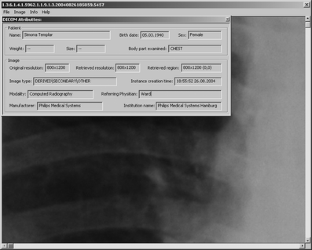

The idea for softcopy viewing of medical image outside the radiology reading room spread among the scientists in various fields for several years. An image could be read on workstation of all types, from desktop across movable to handheld. Benefits are numerous and continue to grow as physicians use them discovering new usage cases. Proposed solutions vary with PACS architecture invasion level, communication and storage image formats, and utilization. We employ JPEG2000 standard because of its high (lossy/lossless) compression ratio with minimal spatial distortion, retrieval-oriented storage, and streaming. It is embedded in PACS as the DICOM Private Data Element containing JPIP parameter string, so-called DICOM2000. The DICOM2000 message is transparent for standard DICOM devices at the slightest level of invasion. Thanks to sophisticated JPEG2000 streaming, medical image becomes suitable for any resolution and quality display and (wireless) networks. The solution is validated on the ACR/NEMA standard test set of PACS images.